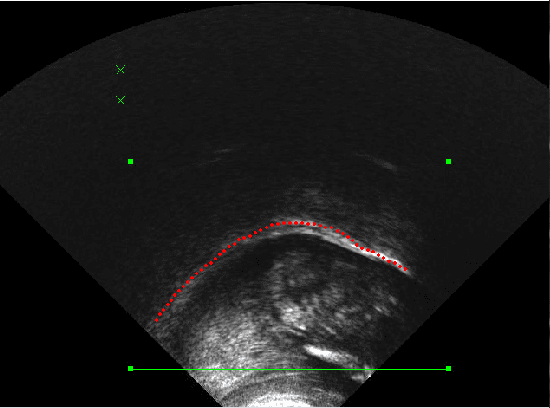

This paper presents a new database consisting of concurrent articulatory and acoustic speech data. The articulatory data correspond to ultrasound videos of the vocal tract dynamics, which allow the visualization of the tongue upper contour during the speech production process. Acoustic data is composed of 30 short sentences that were acquired by a directional cardioid microphone. This database includes data from 17 young subjects (8 male and 9 female) from the Santander region in Colombia, who reported not having any speech pathology.